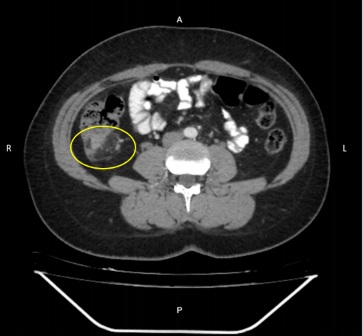

Paciente femenina, que cursa la tercera década de la vida, con antecedente de apendicetomía hace siete años, ingresó a clínica de tercer nivel por un cuadro de una semana de evolución caracterizado por dolor abdominal localizado en la fosa iliaca derecha, sin fiebre ni vómitos ni otra sintomatología. Al examen físico, presentó abdomen globoso a expensas de abundante panículo adiposo, levemente doloroso a la palpación en la fosa iliaca derecha, sin signos de irritación peritoneal. Sus signos vitales fueron estables: frecuencia cardiaca de 72 latidos por minuto, tensión arterial 115/75 mmHg, temperatura 36 °C. El recuento total de glóbulos blancos fue de 13 400 mm3 (90 % de neutrófilos). Finalmente, la ecografía de abdomen total estuvo dentro de los límites normales, por lo que se solicitó una tomografía axial computarizada (TAC) de abdomen total, donde se evidenció apendicitis aguda con cambios inflamatorios regionales (Figura 1).

Figura 1 TAC de abdomen total con signos tomográficos de apendicitis aguda, cambios inflamatorios regionales, sin líquido libre ni colecciones organizadas